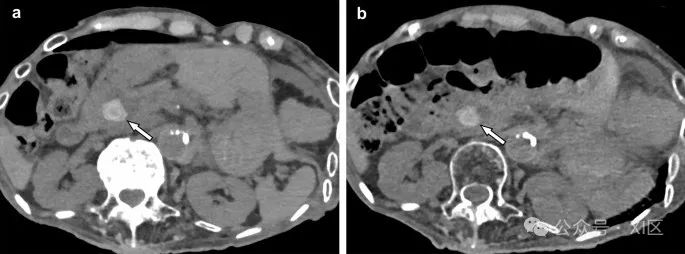

在各种癌症中,胰腺癌的预后显著差,早期发现对患者生存至关重要。胰腺癌通常表现为低血管肿块,但在早期阶段由于其小尺寸和低对比度,常常难以通过诊断成像CT或MRI检测到。光子计数CT的70 keV或以下的虚拟单色图像在胰腺期和门静脉期显著提高了胰腺癌的显著性,与能量积分探测器CT相比(图8)。此外,胰腺癌是一种高度侵袭性的肿瘤,在治疗前确定其侵袭程度非常重要。光子计数CT的高空间分辨率在评估肿瘤侵袭方面也可能有用。

图8 胰腺尾部的小低血管结节(箭头)在胰腺实质期(动脉期)光子计数CT图像上分别在70 keV(A)和50 keV(B)可见。同时,肿瘤的增强(箭头)在平衡期分别在70 keV(C)和50 keV(D)可见。50 keV图像(D)上的延迟增强比70 keV图像(C)上更明显。小的胰腺癌常常在胰腺实质期不可见,但在平衡期仅作为延迟增强病变可见。光子计数CT获得的低keV图像可能有助于胰腺癌的早期发现。导管内乳头状黏液性肿瘤